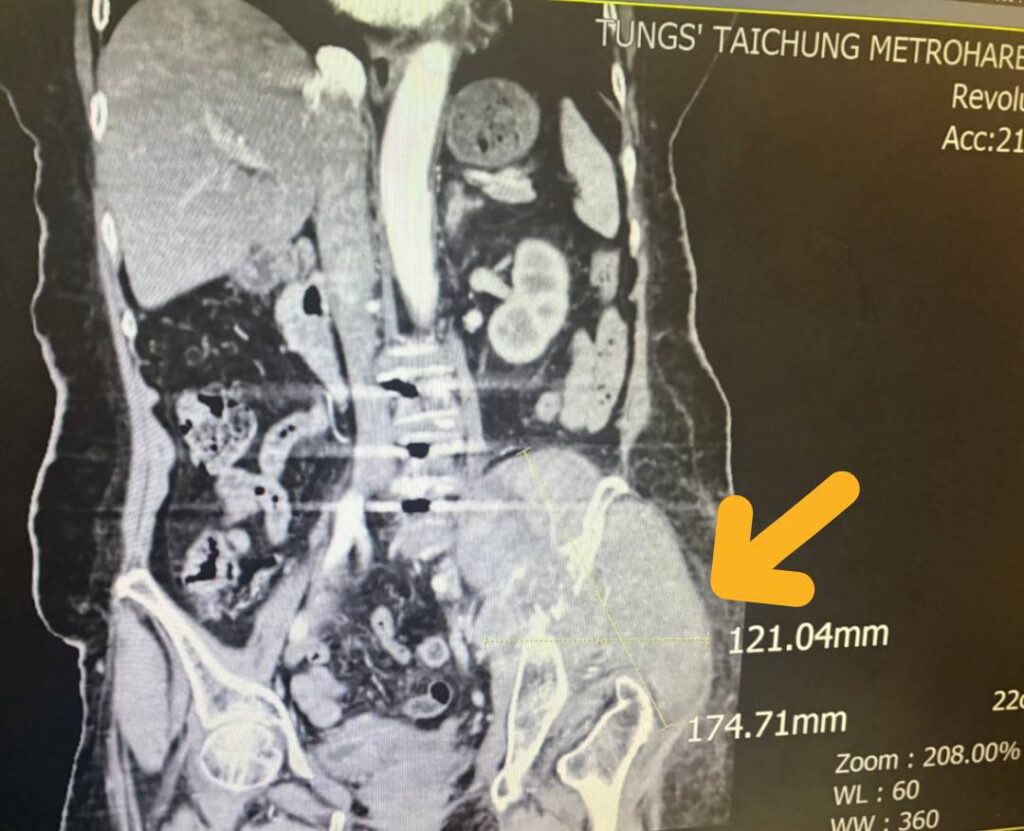

童綜合醫院指出,因腫瘤細胞直徑平均約15公分,腫瘤位置執行手術風險過高,轉由放射腫瘤科葉啟源主任進行銳視刀適應性放射治療,利用空間分割點狀治療方式在局部的位置給予點狀高劑量的放射線,再配合傳統銳視刀治療方式,經過一個月26次治療後,腫瘤已經縮小至9.8公分x10.1公分左右,縮小腫瘤後也讓疼痛獲得明顯改善。

放射腫瘤科葉啟源主任表示,肝樣癌是一種罕見且具高度侵襲性的惡性腫瘤,特點是發生在肝臟以外器官的原發性腫瘤,但組織型態與細胞特徵卻與「肝細胞癌」相似。個案的腫瘤發生位置在骶骨(尾椎上方)。因為初期無任何不適症狀,等到腫瘤大到壓迫到骶叢神經而導致腿部疼痛與無力才發現,因腫瘤太大,若只採用一般治療無法有效消除癌細胞,因此搭配使用最新的點狀式治療,以高劑量消融巨大、抗放射性腫瘤,同時利用傳統治療劑量梯度保護周圍的健康組織與器官。讓腫瘤明顯在三個月內縮小了2×7公分,緩解骶叢神經受壓迫的情況,改善患者的疼痛與行動能力。